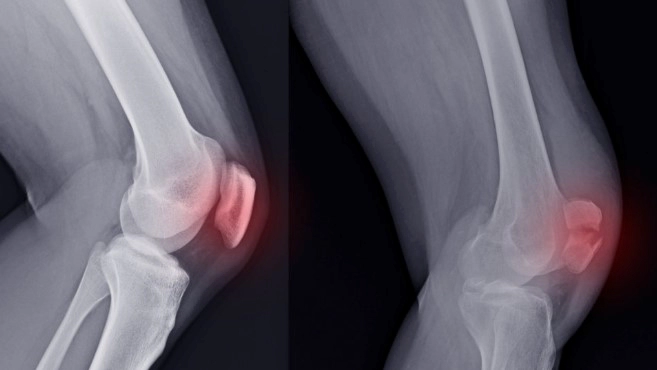

슬개골 탈구는 무릎 관절에서 슬개골이 자리를 이탈하는 부상으로, 이는 종종 극도의 통증과 불편함을 초래하며, 일상 생활에 상당한 지장을 줄 수 있습니다. 이는 스포츠 활동 중 또는 심한 사고로 발생할 수 있습니다. 이에 슬개골 탈구의 주요 증상 6가지를 자세히 알아보고, 슬개골 탈구 수술 및 재활에 대한 내용과 영상을 살펴보겠습니다.

가장 심각한 슬개골 탈구의 증상 중 하나는 무릎의 가시적인 변형일 수 있습니다. 슬개골이 원래 위치에서 크게 이동한 경우, 무릎의 형태나 구조가 훼손되어 보일 수 있습니다. 이는 무릎 뒷부분이 비정상적으로 부풀어 오르거나, 무릎이 정상적인 위치보다 앞으로 또는 뒤로 늘어나 보이는 형태로 나타날 수 있습니다.